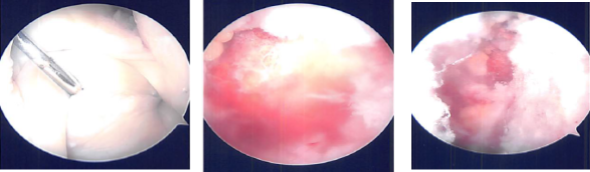

Arthroscopic set up was done and the time-out was called. A lateral entry portal was made and an arthroscope was inserted. The arthroscope was moved to the medial tibiofemoral compartment. A medial entry portal was made in a far medial position so as to reach the lateral meniscus easily. Shaver was introduced.

Examination of the medial compartment showed intact meniscus as well as chondral surfaces. Debridement of the intercondylar notch was done to remove the ligamentum patellae. The ACL was intact.

Examination of the lateral tibiofemoral compartment showed tear in the anterior horn as well as partial tear in the anterior root. The tear in the anterior horn was in the red-white zone and it was decided to repair it. Debridement of the anterior root of the lateral meniscus was performed.

The tear was prepped with the use of meniscal rasp and shaver. Outside-in repair was planned. Meniscal mender was opened and the straight needle was passed percutaneously laterally through the meniscus tear. The probe needle was advanced at the side of the straight needle through the tear.

Once it was in, the snare was passed out of the probe needle and PDS suture was passed through the straight needle The PDS suture was retrieved. A skin incision was given connecting the two sutures.

The PDS suture was replaced by #2-0 FiberWire. The repair was checked arthroscopically and found to be in a satisfactory position. The suture was knotted on the outside.

Examination of the rest of the lateral tibiofibular femoral compartment showed intact meniscus in the posterior horn as well as intact bone and cartilages. Examination of the patellofemoral compartment showed intact cartilage and no maltracking.

The final picture was taken and saved. The knee was thoroughly irrigated. To perform microfracture chondroplasty in the intercondylar notch to release the marrow into the knee to allow a good healing environment. Knee was drained completely.

Intraoperative images